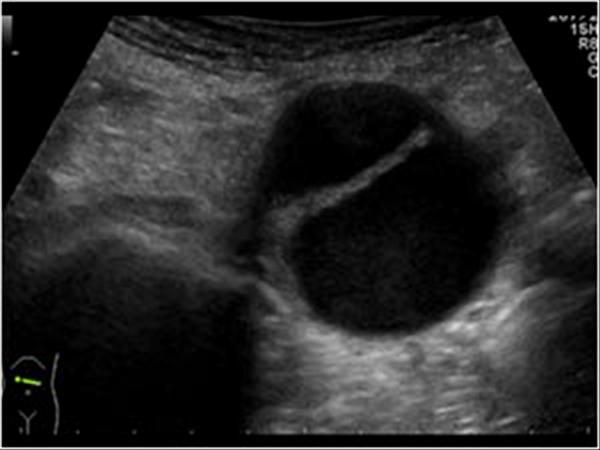

Pancreatic Psydocyst

Spherical fluid collection of pancreatic enzymes that arise from inflamatory, necrotic and hemorrhage processes of the pancrreas

persistently elevated amylase and lipase

Pancreatic Psydocyst

Spherical fluid collection of pancreatic enzymes that arise from inflamatory, necrotic and hemorrhage processes of the pancrreas

persistently elevated amylase and lipase

Pancreatic Psydocyst

Spherical fluid collection of pancreatic enzymes that arise from inflamatory, necrotic and hemorrhage processes of the pancrreas